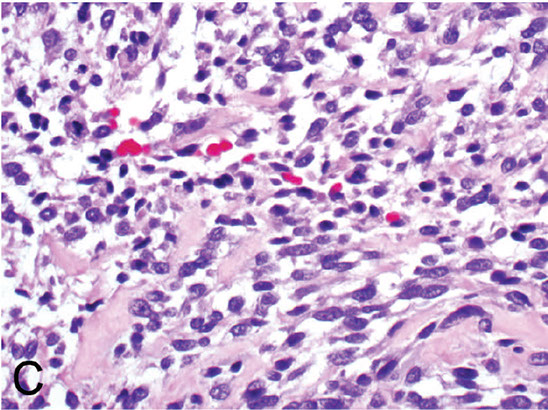

Epithelioid Sarcoma

Distal extremities of young adults, mostly on flexors of fingers, knee and forearms (places c little subQ fat)

- M:F = 2:1

- slow growing hard nodule that usually becomes ulcerated (which may mimic ulcerating SCC)

- usually 3-6 cm

- spreads along aponeurosis in centripetal pattern and can ulcerate the skin

2 types:

1) Conventional (classic or distal)

- has pseudogranulomatous appearance and is MC in acral spots

- Young adults, M>F, not as aggressive

2) Proximal type

- has epithelioid morphology and is MC in proximal / truncal sites such as the pelvic and perianal regions

- more aggressive course

Imaging: speckled pattern of calcification, cortical thinning of underlying bone; MRI good to eval extent of lesion

Micro: nodular arrangement c central necrosis (looks pseudogranulomatous), also epithelioid appearance c red cytoplasm and peripheral spindling, reminiscent of a granuloma

- nodules may be more or less well-circumscribed

- cells range from large oval / polygonal to plump spindle-shaped cells

- loss of cohesion and hemorrhage can mimic angiosarcoma

- 10% have calcification / bone formation

Genes: loss of SMARCB1 cr 22q11 (just like malignant rhabdoid tumor of infancy and AT/RT)

IHC: (+) cyclin D1 (nuclear), EMA, vimentin, CK8/19, CD34 (in 50%, do not confuse c vascular neoplasm), ERG (in 60%), FLI1 (in 70%)

- negative S-100, CK5/6, neurofilament protein, CEA, vWF, SMARCB1, HHF-35, INI-1 (loss of INI1 in ~90% of conventional and proximal types)

- co-expression of CK and CD34 unique to epithelioid sarcoma and epithelioid angiosarc)

DDx: necrotizing infectious granuloma, necrobiosis lipoidica, granuloma annulare, rheumatoid nodule, epithelioid MPNST, melanoma, epithelioid sarcoma-like hemangioendothelioma, ulcerative SCC (cyclinD1 negative, CK5/6 [+])

Tx: excision (amputation), rads

Px: Poor, most die from the dz; high rates of local recurrence and mets (to lung and LNs)

- poor px factors: proximal tumors, large size (5 cm cutoff), deep tumors, hemorrhage, mits, necrosis, rhabdoid features, angiolymphatic invasion, inadequate excision, vasc invasion

- 1/2 die before 10 yrs

Epithelioid sarcoma. A, The tumor shows epithelioid morphology and moderate to severe cytologic atypia. The lesional cells are positive for cytokeratin (B) and erythroblast transformation-specific transcription factor (ERG) (C) and demonstrate loss of nuclear integrase interactor 1 (INI1) (D) (hematoxylin-eosin, original magnification x200 [A]; original magnifications x200 [B through D]